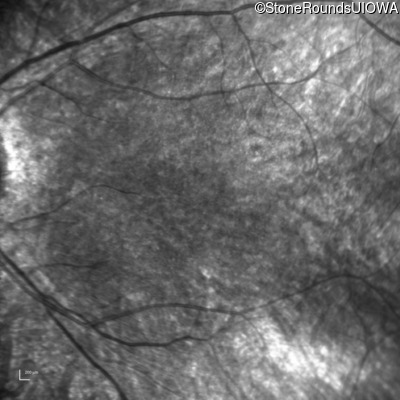

Age at visit: 10 years

Age at visit: 11 years